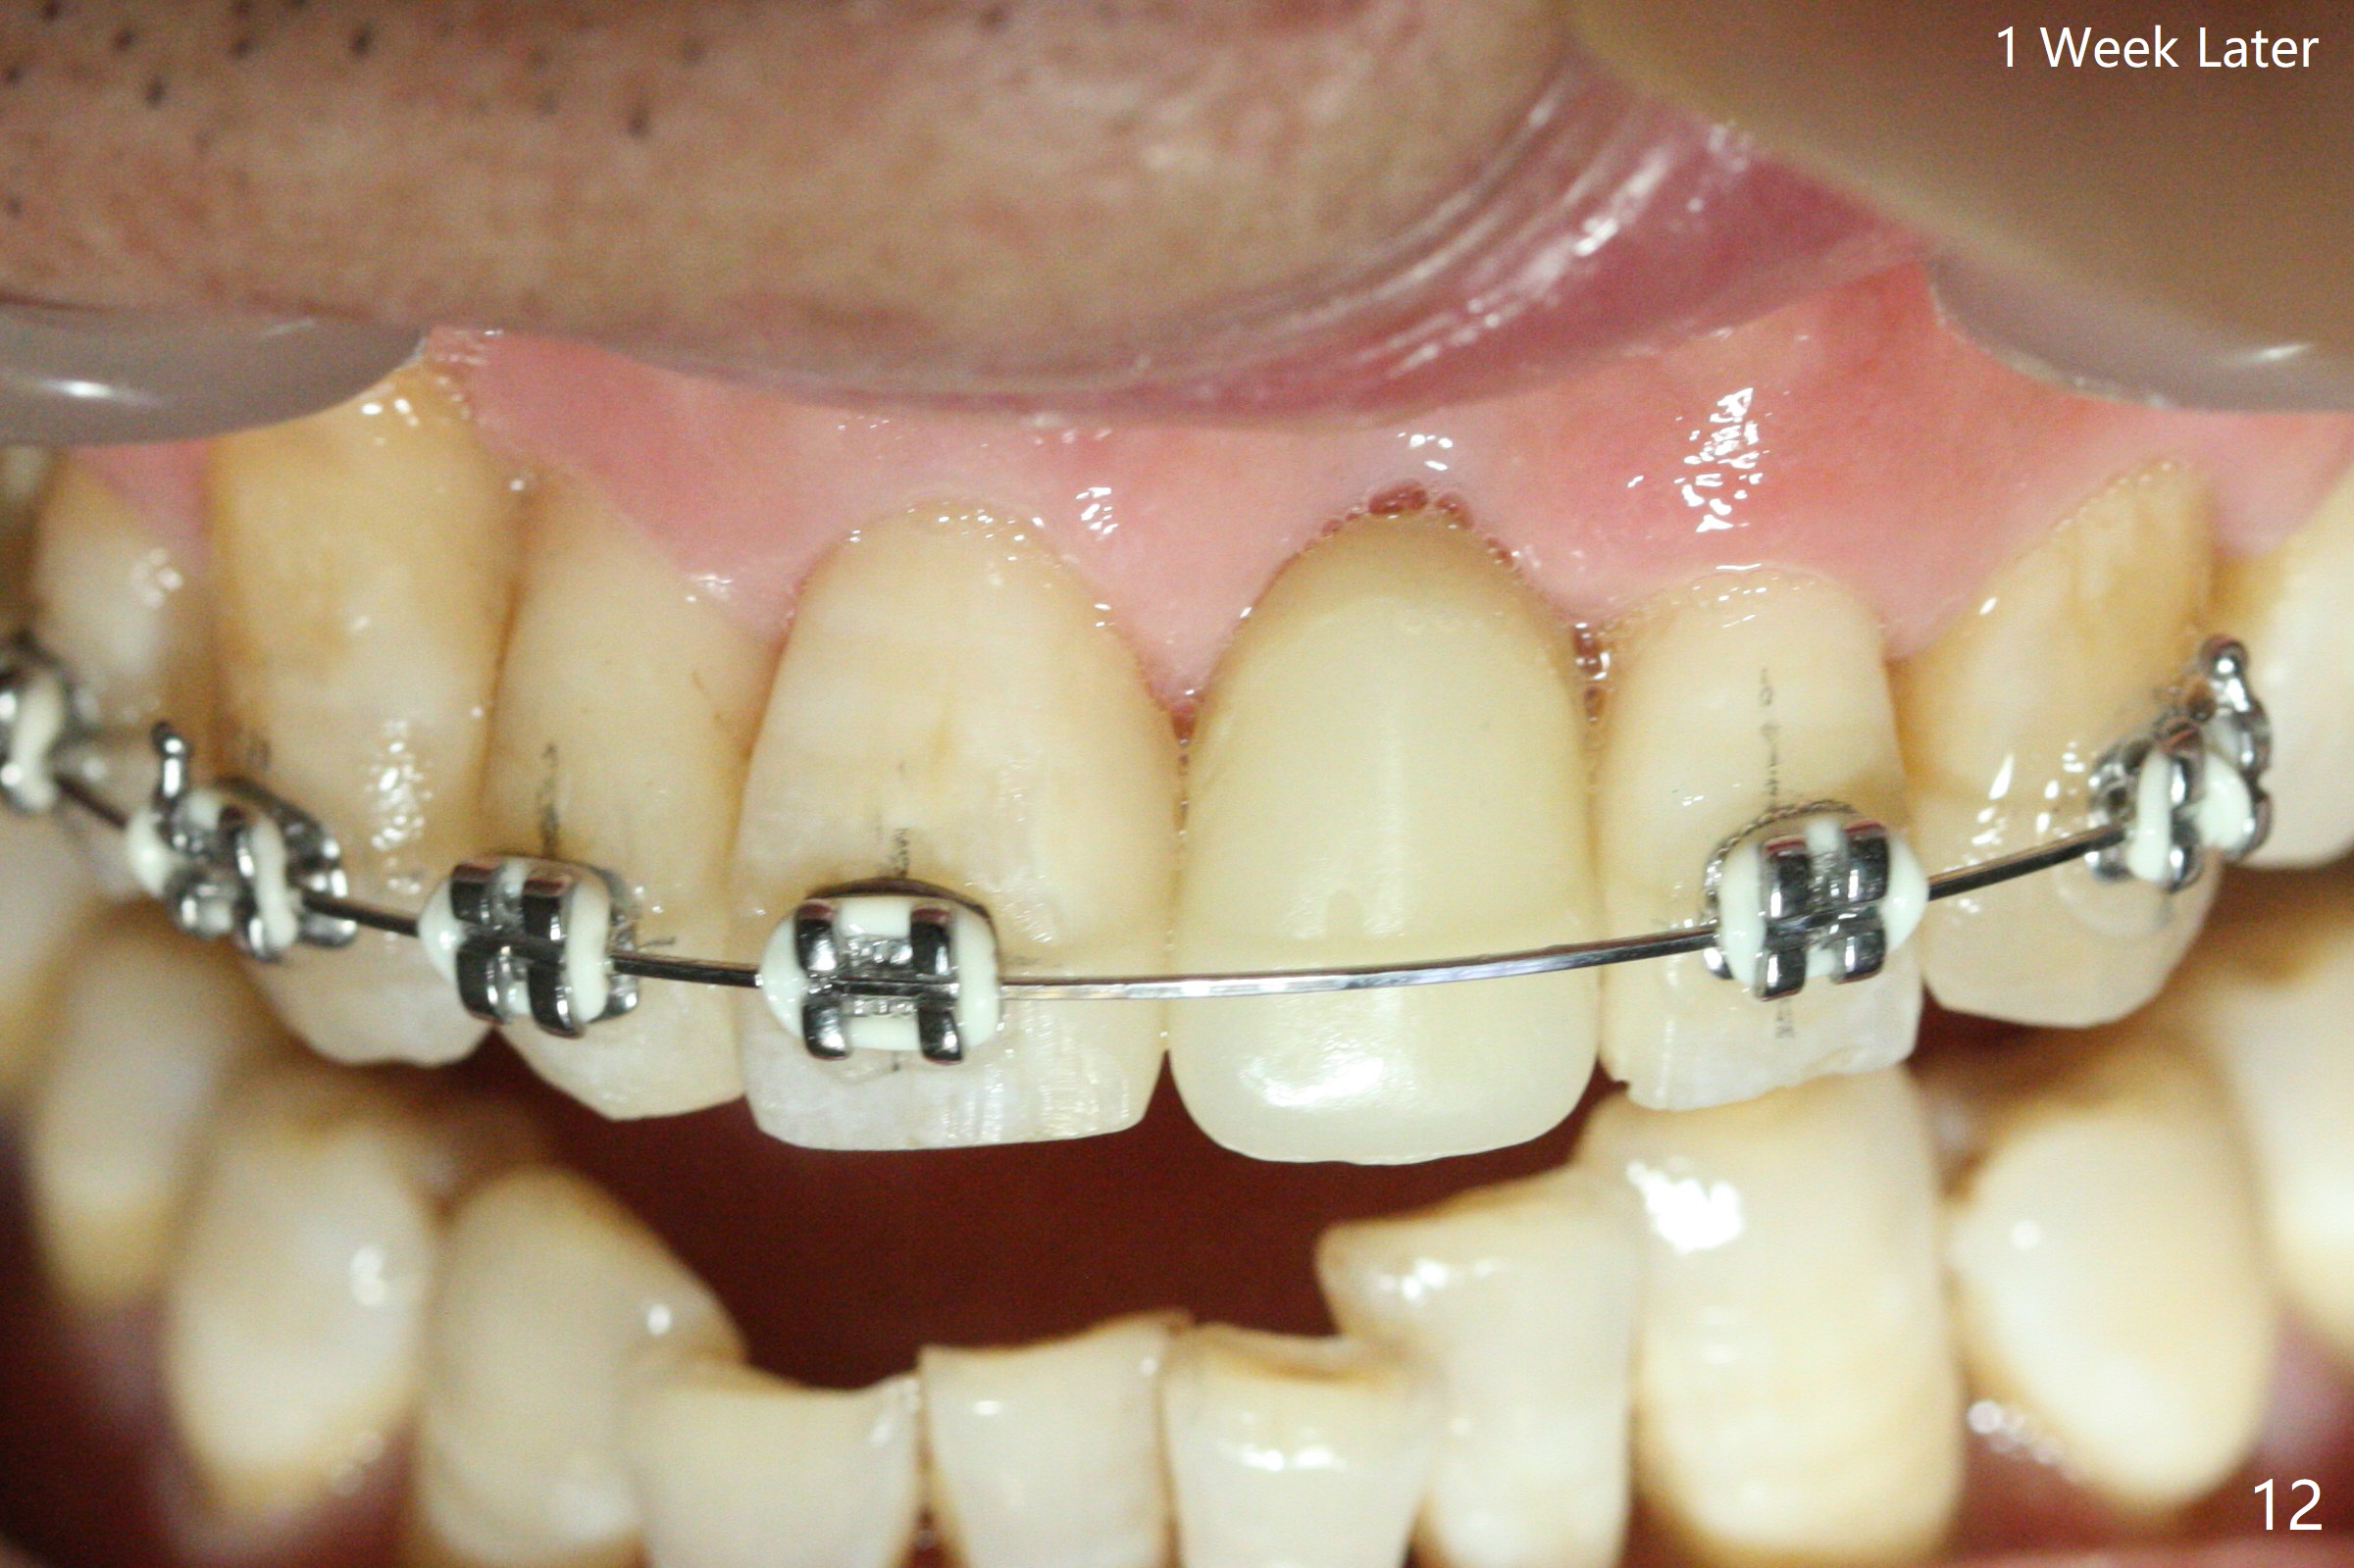

Nearly 7 months postop, the immediate provisional at UL1 is removed; with the mesial reduction of UL2 from 7 to 6 mm (Fig.1), an angled abutment is to be changed (4.5x15 degree, 2 mm cuff). A new provisional (Fig.2,3) co-incides with the facial midline. Brackets will be placed between UR4 to UL3 except UL2 (symptomatic once with chronic periodontitis) with initial proximal reduction between UR1-4 in preparation to correct cross bite of UR2. Twelve days later, the patient returns for UR5-UL3 bracketing after UR1-4 initial proximal reduction with 14 niti wire (Fig.4-6). UR1 moves mesial 20 days post open coil spring (Fig.7 arrow), while UL1 debracketes after permanent re-cementation of the temporary crown last visit (*, no re-bracketing, since it appears not essential). Before placement of 20 ss wire, diastemata are created by proximal reduction (Fig.8 *). In fact UR1 moves mesial, while UR3 does not move distal with the open coil. With placement of UR6 (implant) molar band, UR3 is distalized effectively. With sling shot, UR2 is almost labialized in one appointment (Fig.9). After consolidation of the diastemata between UR1-6 with power chains following UR2 cross bite correction (Fig.10), the restoration space for UL1 seems to be too large (Fig.11). Next visit, check the midlines, take 1-2 PAs for #7-9 and determine whether a straight abutment should be changed back and whether composite should be placed UR1 mesial to reduce the space. One week later, composite is added to the mesial surface of the tooth #8 to increase its width, while the provisional at #9 is relined to improve the interdental papilla (Fig.12). Minimal bone loss at UR2 is observed 8 months post banding (Fig.13), while the socket at UL1 seems to have healed except the most coronal 1 year 3 months postop (Fig.14 *). The margin of the abutment should be uneven, more coronal proximal than buccopalatal (Fig.15). The final crown has an open margin, partially due to less ideal trajectory (Fig.16 (black line: ideal trajectory, nearly 1 year 4 months postop)). Guided surgery could solve the problem. Sticky bone may restore the buccal plate defect. Die shows that the implant is palatally placed (Fig.17). CT will be taken to determine whether the implant perforates the palatal plate.